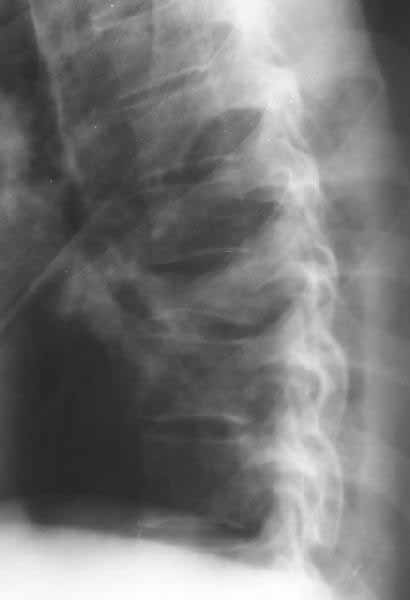

A male 39 years old some times rolled within a car June 12. Clinically no neurological deficit. Does the case require operative reduction/stablization? If no how would you manage the case?

A CT would be helpful to determine if there is middle column involvement. Also it would help determine if the posterior interspinous ligament is intact (lack of interspinous widening. The available images appear to show an anterior column only injury. If other imaging tests confirm this combined with normal neurological function nonoperative treatment with a hyperextension brace or nothing is appropriate.

Agreed, except that loss of posterior vertebral body height on the lateral radiograph suggests middle column involvement as well, and therefore a diagnosis of burst fracture. This is confirmed on the AP by (albeit subtle) widening of the pedicles at the level of injury. In keeping with this diagnosis, the lateral also suggests retropulsion of fracture fragments into the canal. I concur that unless there is associated facet subluxation or interspinous widening on CT (possible, but unlikely given the well-maintained alignment and given that on the AP radiograph the spinous processes seem reasonably equidistant) this is a stable burst fracture that I would treat with a TLSO for 3 months.

This presumablly is a stable compression of the body of T8 or thereabout, without neurology. Keep him in bed until the acute pain subsides and then start him on physiotherapy.